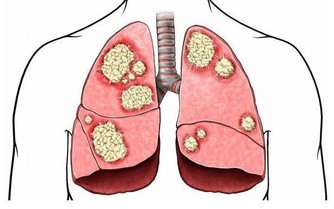

面部浮腫,是臨床上最為典型的腎臟疾病的表現。尤其是尿毒症患者,大多數尿毒症患者在早期都會出現不同程度的浮腫的症狀。

這主要是由於人體腎臟功能受損,導致腎臟的代謝功能異常,從而使得人體的水液循環受阻,使得大量水分聚集在人體內所致。